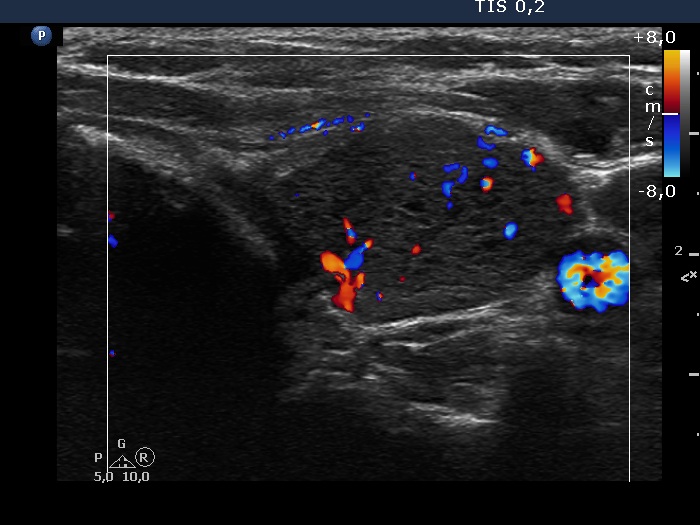

Second examination 3 years later (second, fourth and sixth rows of images):

Ultrasonography. Compared with the previous examination, both the number and the size of discrete lesions in the thyroid have increased.